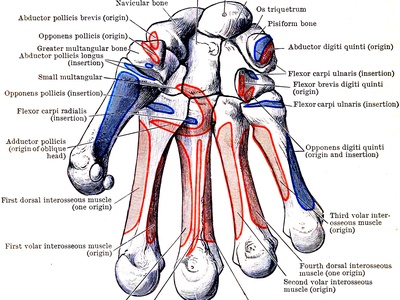

Radial sesamoid (thumb)

A small sesamoid on the radial (thumb-side) face of the thumb’s MCP joint, embedded in tendons of intrinsic thumb muscles. It boosts pinch strength and smooths tendon action. It can be involved in arthritis or fracture after trauma.

Ulnar sesamoid (thumb)

The ulnar sesamoid sits on the inner side of the thumb’s MCP joint within intrinsic muscle tendons. Together with the radial sesamoid it stabilizes the joint and can cause pain or fracture after injury.